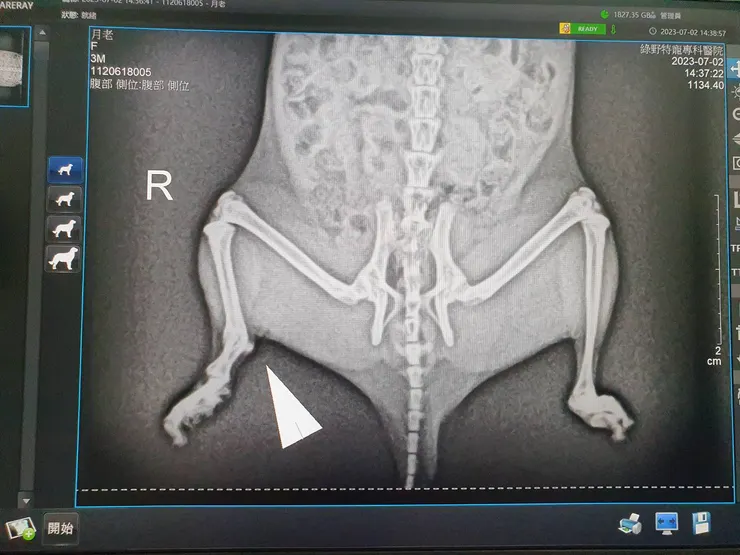

本次回診另外一個目的,是因為六月底與月老互動時發現,鼠鼠右後腿被毛覆蓋的地方,有不自然的突起物。經過李醫師X光檢查後,發現至少為數月前的骨折舊傷,現在已經痊癒。

月老的骨質從X光片上看起來健康正常,推斷有可能是在原生環境時因意外骨折,後因骨頭自癒,導致有突起物。

目前並沒有明顯影響走路及攀爬等動作,故僅拍X光做確認,無後續其他侵入性治療。